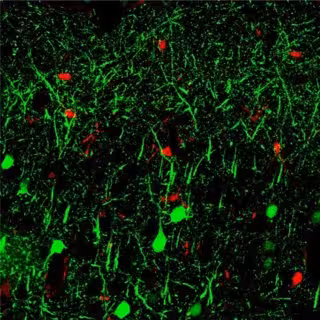

Archivo - MicroARN 142

Archivo - MicroARN 142 - HUI-CHEN LU, INDIANA UNIVERSITY - Archivo